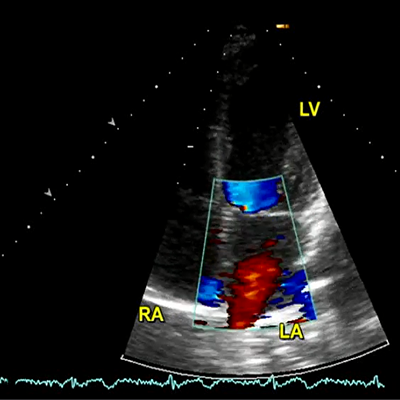

MR severity during echocardiographic examination

MR severity during echocardiographic examination

MR severity during echocardiographic examination

MR severity during echocardiographic examination